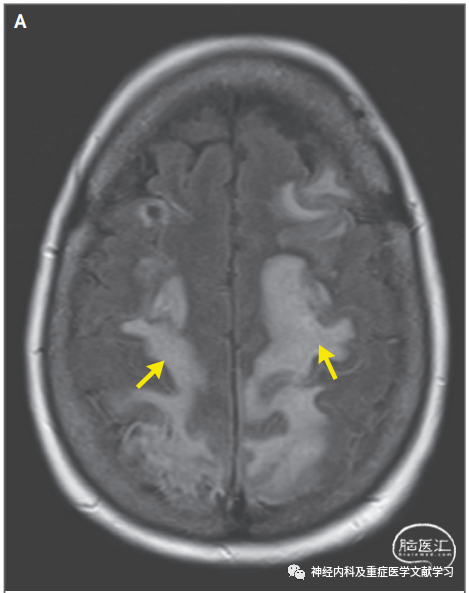

图4PRES患者非典型影像学改变

一名57岁的男子在肾移植后患有多灶性肌阵挛、2019冠状病毒病和慢性肾脏疾病,目前正在接受免疫抑制治疗。图A显示患者颅脑轴向MRI FLAIR图像,小脑半球弥漫性融合信号改变(箭头)。B图为弥散加权图像,这些区域的信号变化不对称。表观扩散系数图像(C组)未显示这些区域的变化,提示脑组织没有梗死。